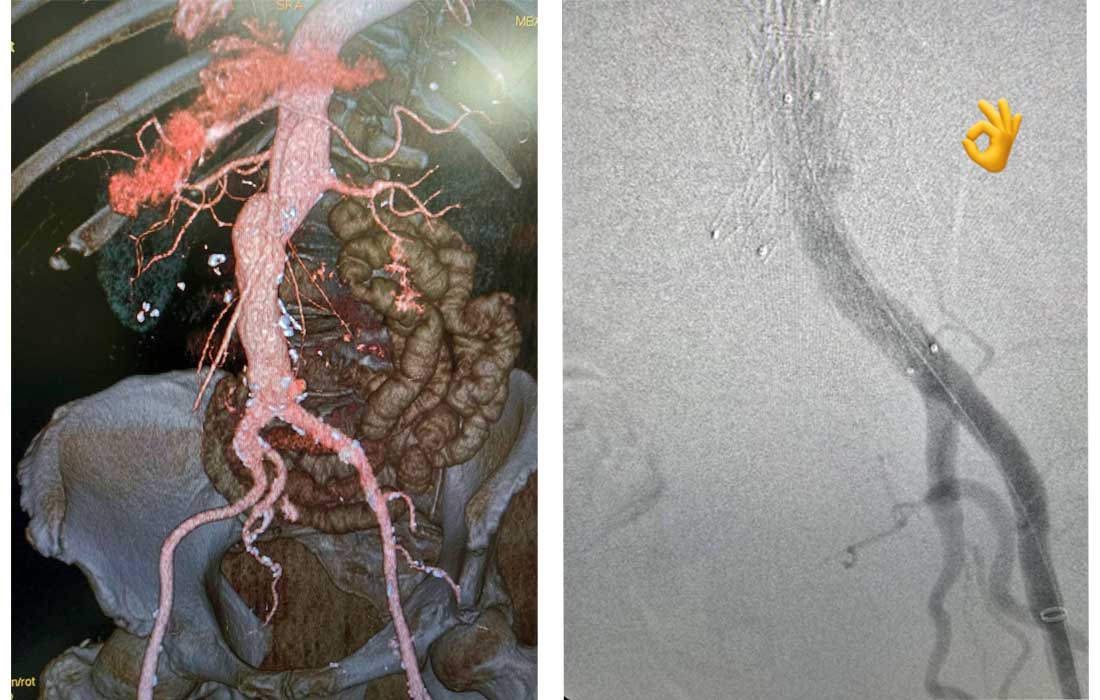

Оперираха аневризма на коремна аорта с CO2 за първи път в България при пациент с тежка алергия към йодeн контраст

Съдови хирурзи от УМБАЛ „Тракия“ извършиха успешно лечение на полианевризми на коремната аорта с помощта на автоматичния инжектор на контрастни вещества на периферно-съдово ниво Angiodroid. Вместо високомолекулярен йоден контраст, апаратът инжектира в кръвта въглероден диоксид, който също е рентгено контрастен и след 4-5 минути пациента го издишва. Напълно безопасен е и не се налага след операцията кръвта да се пречиства с диализатор от креатинин.

Дигитално-субтракционната ангиография с въглероден диоксид (CO2-DSA) е все по-често използвана техника при ендоваскуларна аортна репарация (EVAR) и фенестрирана (разклонена) EVAR (F/B-EVAR). Тя се използва за предотвратяване на постоперативно влошаване на бъбречната функция (PO-RFW) и при пациенти с алергии към контрасти материи, посочва д-р Павел Атанасов.

Лекарите установяват множество разширения по абдоминалната аорта, подобни на торбички, които тръгват от отделянето на бъбречните артерии и продължават по хълбочните артерии на двата крака, където аневризмите са достигали до над 2 – 3 сантиметра.

„По време на операцията аневризмите на аортния и по илиячния сегмент бяха изолирани, след като успешно изолирахме кръвотока, благодарение на ясните анатомични ориентири, получени от визуализацията с CO2 и устройствата, с които е оборудвана операционната“, посочи д-р Бисеров.